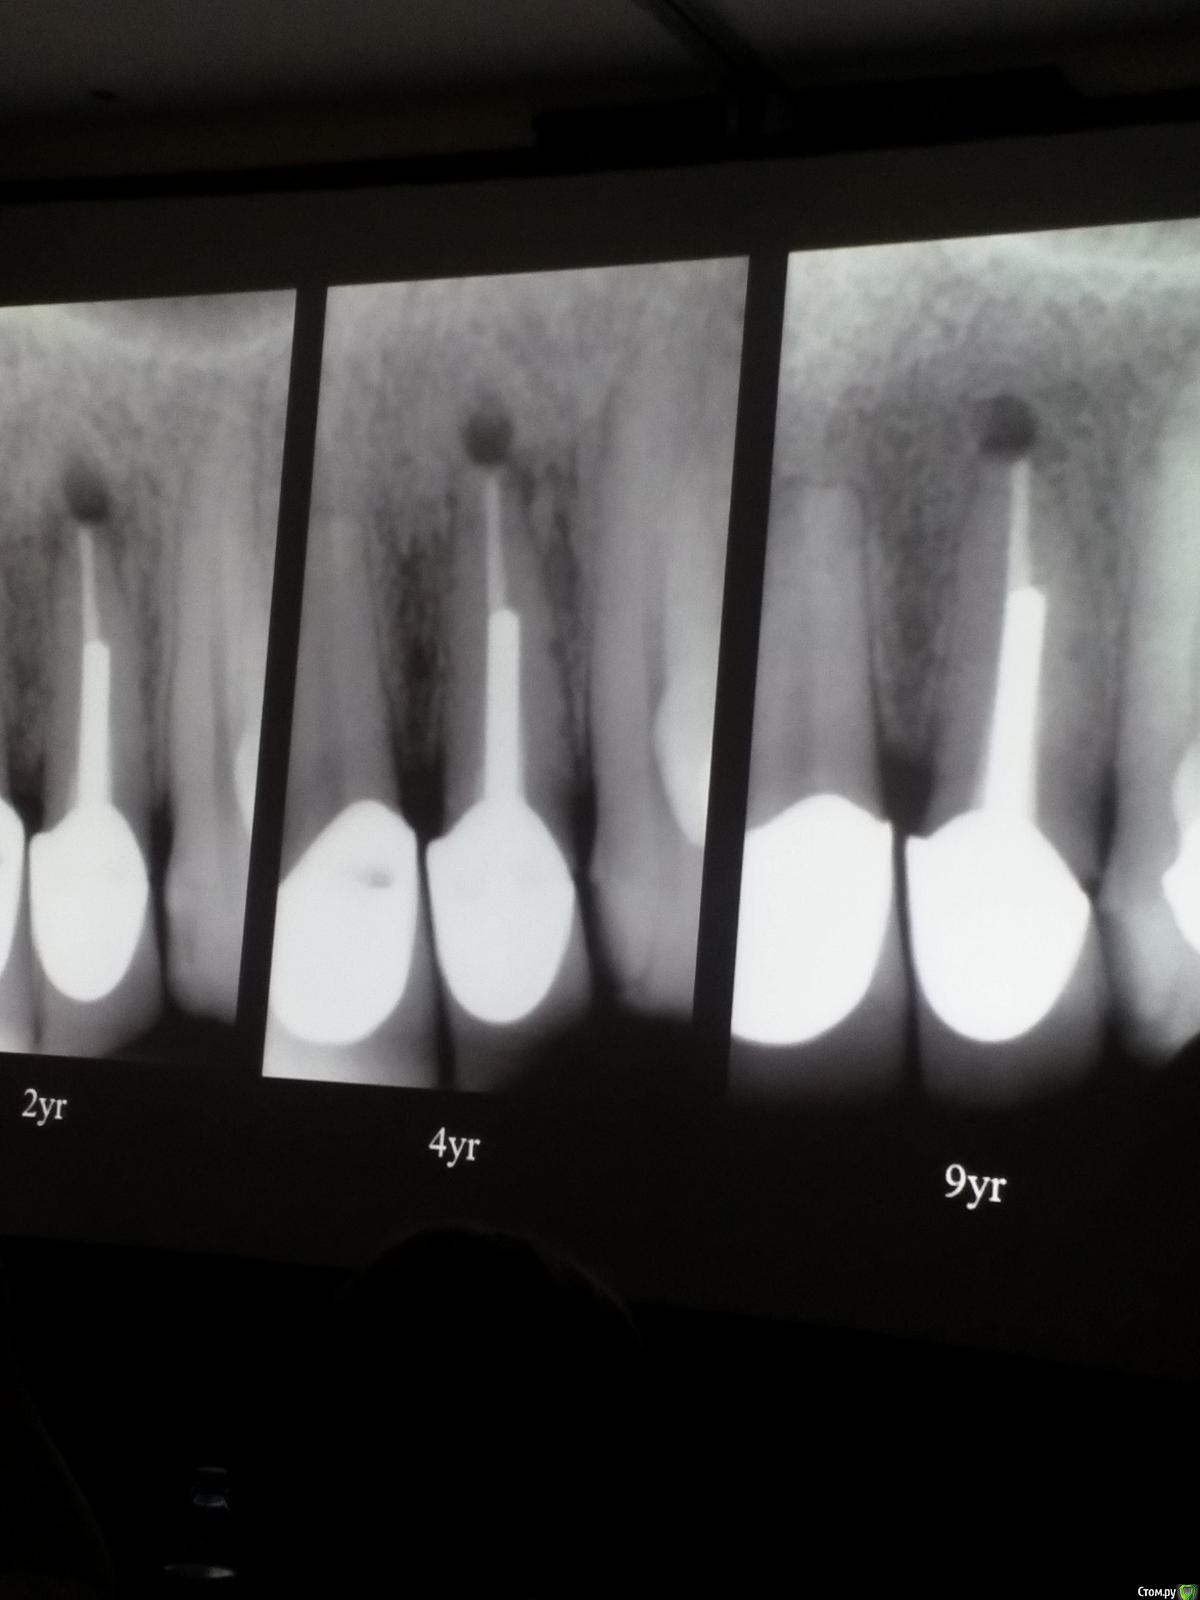

Популярный пост Kolchanov Опубликовано 12 марта, 2017 Автор Популярный пост Поделиться Опубликовано 12 марта, 2017 Второй день.1) Дезинфекция зуба и раббер дама перед работой. Вначале установка системы, потом протирка тампоном 30% перекиси, потом протирка всего йодинолом. Потом преп, потом повторение и только потом доступ к к/к. Все старые реставрации надо убрать, кариес убрать, противник лечения через коронку.2) Гидроокись на неделю. Замешивает на стерильном физрастворе. При необходимости повторяет. Т.е. в случае сохранения свища, симптоматики, экссудации, запаха. Если свищ не исчезает после трех смен временных вложений, то хирургия.3) Пломбирует латеральной компакцией. Лучше контроль длины обтурации.4) Высушивание канала стерильными штифтами, на рабочую длину минус 1мм. После высушивания штифт оставляется на 60с. в канале и должен выйти сухим.5) Определение рабочей длины. Витальные случаи. АЛ должен три раза дать одну и ту же картинку в определенной точке + проверка RG. Девитальные случаи. На АЛ полагаться сложно, т.к. из-за наличия резорбции констрикции может врать, больше ориентируется на RG.6) Использует ЦОЭ силеры. Резорбируются при незначительном выведении. Резорбируются в канале, позволяя закрыть апекс цементоподобной тканью. Вот так вот.Случаи исчезновения силера, как за пределами канала так и в канале7) Выведение материала (не важно какого) в большом объеме способно вызвать защитную реакцию тканей. Которая должна пройти спустя некоторое время. (иногда это будет 25 лет J Случай 1ый. Студенты наломали инструментов. Периодонтит на RG через год. Резекция и гистология. Бактерий не обнаружил. Да, маленькое замечание. Каждый препарат дает 500-600 срезов. И ищет он на всех. Объем работы, конечно….Случай 2й. Его собственный. Периапикальное поражение, обнаруженное на реколле через 10 лет зажило еще через 15.8) «Функционирующий зуб» считает результатом неприемлемым. Осталась инфекция с которой надо что-то делать. То, что бактерий можно замуровать в дентинных трубочках и под пломбировочным материалом, считает неправильным. Продукты метаболизма один фиг будут просачиваться и могут поддерживать реакцию воспалительную.Случай. Синее – маленькая кучка микробов, предположительно, препятствовавших заживлению очага.9) Биопленка на поверхности корня может принимать вид кальцификатов (камней) и тут уже только хирургия в помощь. При длительном существовании свищевого хода, например.Черное - это камни вокруг апикального отверстия. И гистология их с кучей синих микробов.Здесь камни на фуркации и отсутствие заживления и свищ даже после ретроградной обработки и пломбировки.А здесь вообще чертова уйма камней. И зацените разветвление канала в этом боковом резце (последнее фото препарата). 10) Реваскуляризация.В некротических случаях дентина не образуется, т.к. одонтобластов нет и не будет новых. Образуется та самая бог знает какая ткань, которая даже и с корнем не связана может быть. Суть здоровый дентикль-петрификат. А в витальных это не реваскуляризация, а обычное формирование корня. Так что нечего тут.11) Трещины дентина.Советует расшивать, братья и сестры. Без фанатизма, если нет симптоматики, но, по возможности максимально. Если есть симптоматика, то там уже по обстоятельствам. Чертова уйма микробов там и ползет, ползет к пульпе. Надеюсь, что еще раз этот замечательный Доктор приедет. Схожу с удовольствием. 2 23 Ссылка на комментарий

Популярный пост Kolchanov Опубликовано 11 марта, 2017 Популярный пост Поделиться Опубликовано 11 марта, 2017 (изменено) Товарищи, скажу я вам...........Вкратце. Может я где-то что-то и приврал, надеюсь, кто еще был, поправят. Честно говоря немного прибалдел от уровня Доктора. Очень, очень высоко! Приедет еще раз, пойду еще. 1) Фиссуры зондирует острым зондом и выпиливает все дотла. По факту у него уже пломбы, а не герметизация.2) Bite-wing у первичных пациентов всегда.3) Если кариес диагносцирован, то лечить его, пофиг какой он там. Эмали, дентина…4) Препарирует до твердого (или до вскрытия J ). CAD, СID… в топку. Кариес маркером не пользуется, проверяет острым зондом/экскаватором. Вычищает все дотла. Считает, что даже небольшое количество бактерий в дентине под пломбой вызывают хроническое воспаление в пульпе. С его слов у него на контроле где-то 500 вскрытий, не удивительно при таком подходе к очистке.5) Тщательная изоляция. Коффер порвался – меняет. Большое значение герметичности реставрации. под замену6) Критерии обратимости и необратимости.Гистологически, обратимый тот, что без абсцессов в пульпе, но клинически это понять нельзя, только предположить.Здесь был бы обратимый, если бы не удалил. Нет микробов в пульпе. Линия - граница обработки.Покрытие 27 лет назад. Dycal, СИЦ, композит. От дайкала одно воспоминание.7) Вскрылись. Размер перфорации, возраст и прочее не играют роли, важно только состояние пульпы, т.е. диагноз.Примеры перфораций.8) Кровотечение останавливает стерильным ватным шариком. Если останавливается, то покрытие, если нет, то пульпотомия или пульпэктомия.9) Использует гидроокись кальция (порошок), перекрывает Dycal или СИЦ. Потом восстановление Нередко под IRM, потом все убирает (через пару-тройку месяцев) и смотрит, что получилось. Порой приходится повторять! Использует и МТА, его тоже убирает.10) Наблюдение 6мес, 1 год, 2…. Все может провалиться и через месяц и через 24 года.Примеры проваловНиже - 24 года спустя появилась дуля. 11) Неравномерная облитерация полости зуба на RG (после покрытия) – признак текущего хронического воспаления, где-то остались микробы. Рекомендует эндо.12) Мостик который образуется – это не дентин! И одонтобласты не регенерируют и новые не образуются. Что это такое он и сам не знает, но раз это твердые ткани, то и наплевать.Вот фиолетовое это дентинные опилки вмурованные в розовую ткань бог знает кем сформированную.13) Пульпотомия в зубах с несформированной верхушкой и в сформированных, при подозрении на частичное поражение коронковой пульпы. Иссекается стерильным алмазным бором часть пульпы, гидроокись, временная пломба на 90 дней, после повторное раскрытие, оценка результата, восстановление в случае формирования твердых тканей. Гипохлоритом можно мыть, можно не мыть, если мыть, то 0,5-1%.14) В апикальной части пульпа чаще витальна, чем нет.15) Периапикальные поражения возникают по причине поступления токсинов микробов с током крови, а не самих бактерий.16) За апикальные расширения в полностью некротических случаях. Надо механически отодрать биопленку и срезать инфицированный дентин. На ирриганты надежды мало.17) Биопленка на поверхности в 6% случаев.Синенькие пид@расы18) Обработку проводить нежно, краун-даун. Чередовать с H-файлом, чтобы посмотреть докуда распространяется некроз.19) Патенси в витальных кейсах не колоть, сохранять витальную пульпу в констрикции!Формирование еще большего сужения в констрикции за счет сохранения витальной пульпы. Изменено 11 марта, 2017 пользователем Kolchanov 31 Ссылка на комментарий